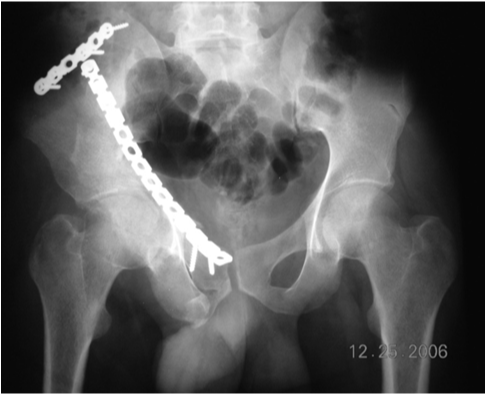

Clinical and radiographic examinations were performed and data were recorded at three months, six months, one year, and two years. At the last follow-up examination, radiographic and clinical grades were assigned (Figure 4). The clinical grade was based on a modification of the system of Merle d’Aubigne and Postel (Table 1).

Figure 4 Follow up radiograph at 3 months showing congruent hip joint and maintenance of anatomical reduction graded as excellent radiologically.